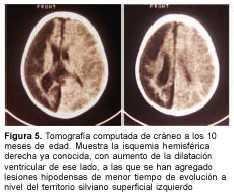

A los 3 meses de edad consultó por hemiplejia izquierda y retraso psicomotor. La tomografía computada (TC) de cráneo demostró un infarto hemisférico derecho (figura 1). Los estudios complementarios pusieron de manifiesto una coartación de aorta torácica descendente, sin evidencia de patología arterial sistémica. A nivel encefálico se estudió con angiografía de cuatro vasos de cuello, que demostró la existencia de una enfermedad de moyamoya (figuras 2 a 4). En ese momento no se consideró el tratamiento quirúrgico y una vez estabilizada se otorgó el alta. La coartación de la aorta no requirió cirugía y no se investigó el eventual nexo con la enfermedad de moyamoya. A los 8 meses de edad comenzó con hemiparesia derecha progresiva, lo que junto a su hemiplejia izquierda agravó su déficit motor severamente. Ingresó al Centro Hospitalario Pereira Rossell a los 10 meses. El examen del ingreso mostraba retardo neuropsíquico, hemiplejia izquierda espástica y hemiparesia derecha severa, que apenas vencía gravedad y no oponía resistencia. Una nueva TC mostró como elemento agregado al infarto derecho previo, una isquemia hemisférica izquierda (figura 5). Se resolvió realizar una revascularización quirúrgica del hemisferio izquierdo. Se intervino (figura 6) en el Servicio de Neurocirugía Pediátrica del Hospital. El procedimiento realizado fue una pialsinangiosis, con disección de la arteria temporal superficial izquierda con galea satélite y la sutura del tejido periarterial a la aracnoides temporal. La evolución posoperatoria fue buena, con recuperación progresiva de la función motora del hemicuerpo derecho. En forma gradual también comenzó a recuperar motricidad de su hemicuerpo izquierdo, anteriormente pléjico, y a mejorar sus performances, comenzando a pronunciar palabras a los cuatro meses, aunque manteniendo un retraso en el desarrollo psicomotor. Al año de operada se constató leve hemiparesia izquierda, ausencia de elementos deficitarios motores a derecha y persistencia de alteraciones en el lenguaje. Una ARM realizada a los diez meses de la operación mostró desarrollo de circulación colateral hacia el área quirúrgica (figura 7). Una TC de control permitió ver el infarto secuelar de hemisferio derecho y disminución franca de la hipodensidad del hemisferio izquierdo a los 18 meses de operada (figuras 8 y 9).

En una primera etapa, a los 3 meses de edad, la paciente fue encarada como un stroke en el lactante, y fue estudiada en ese sentido. Se fueron descartando las causas habituales hasta que se llegó al diagnóstico de enfermedad o síndrome de moyamoya con la angiografía. De acuerdo con las normas diagnósticas del cuadro 1, el caso debía ser catalogado como definitivo por la presencia de los ítems A y C. En ese momento no se consideró oportuno el tratamiento quirúrgico.